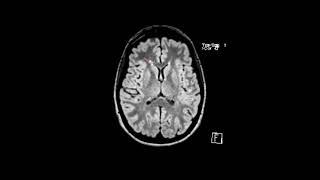

How to read an MRI of the brain | First Look MRI

MS white matter lesions | First Look MRI